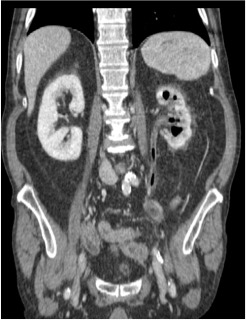

Tomografía computarizada:

- Técnica de elección.

- Agrandamiento y destrucción parenquimatosa.

- Burbujas o tractos lineales de gas.

- Colecciones líquidas y focos de necrosis con o sin abceso.

- Obstrucción renal.

La TC nos permite clasificar la severidad de la PE.

- Grado I: gas en el sistema colector (pielitis enfisematosa)

- Grado II: gas en el parénquima renal sin extensión al espacio extrarenal

- Grado III: a)Extensión del gas o abceso al espacio perirenal. b)Extensión del gas o absceso al espacio pararenal y/o extensión a tejidos adyacentes (psoas…)

- Grado IV: bilateral o pielonefritis enfisematosa en riñón único.